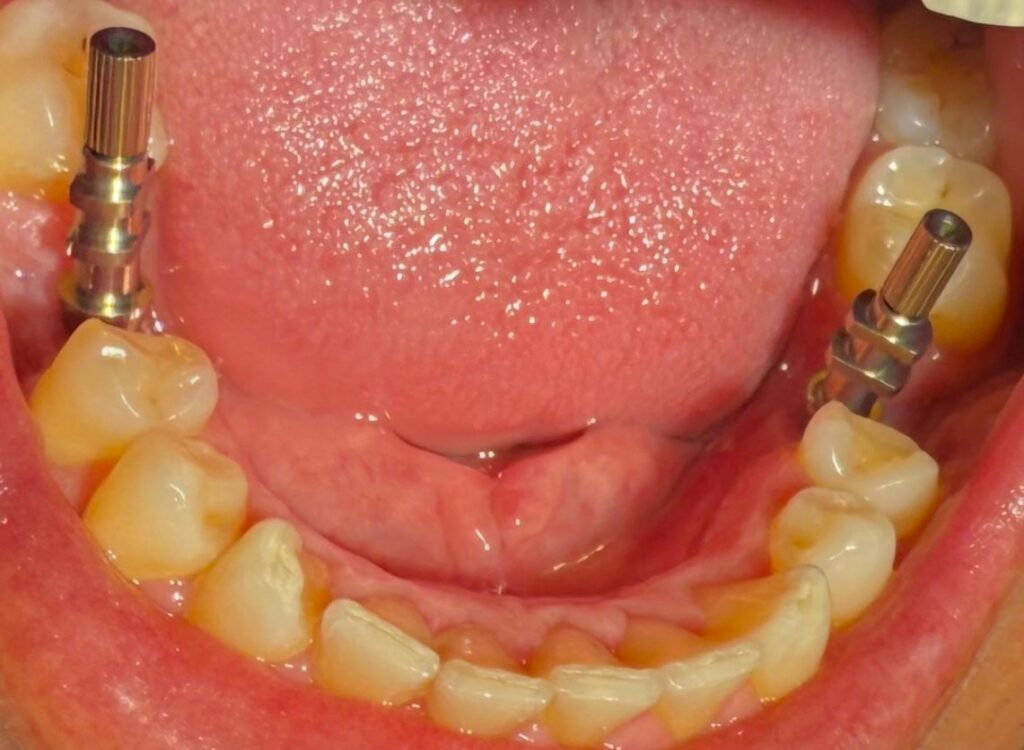

Es muy común que, con el paso de los años, hayamos perdido alguna pieza dental en la parte posterior de la boca. En muchos pacientes que visitan nuestra clínica dental en Puerto del Carmen, vemos un patrón repetido: la falta de una muela en el lado inferior derecho y otra en el izquierdo.

- Cirugía mínimamente invasiva: Colocamos los dos implantes (uno en cada hueco). Es un procedimiento mucho más sencillo de lo que los pacientes suelen imaginar, realizado bajo anestesia local y con un postoperatorio muy llevadero.

- Osteointegración: Es el periodo (generalmente de unos meses) en el que el implante se fusiona con tu hueso de forma natural. Durante este tiempo, el titanio se convierte en parte de tu cuerpo.